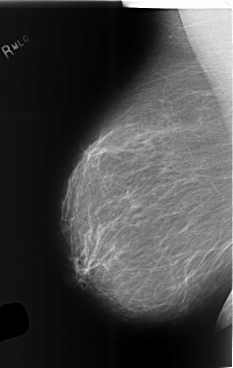

C_0496_1.LEFT_MLO

LEFT_MLO LINES 5752 PIXELS_PER_LINE 3976 BITS_PER_PIXEL 12 RESOLUTION 50 OVERLAY